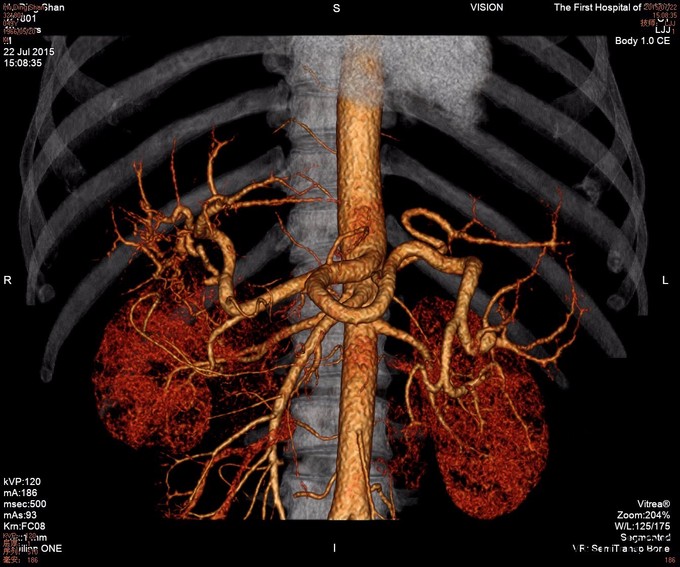

查体:全身皮肤有黄染,见肝掌及蜘蛛痣,腹肌软,腹部可见陈旧性手术疤痕,移动性浊音阴性,肠鸣音正常。 辅查: 腹部MRI:1.肝硬化,脾大,少量腹水,食道下段、胃底及脾门周围静脉曲张。 2.肝内胆管、左肝管扩张,门脉淋巴水肿;腹膜后、心膈角区多发肿大淋巴结,请结合临床。 3.胆囊术后缺如。 4.胰腺体尾部未见显示。